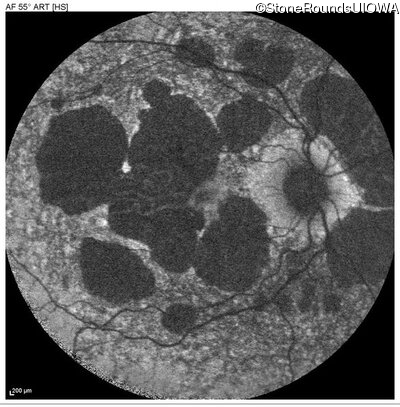

Blue Autofluorescence - Right - 20/20 -3

Exemplar